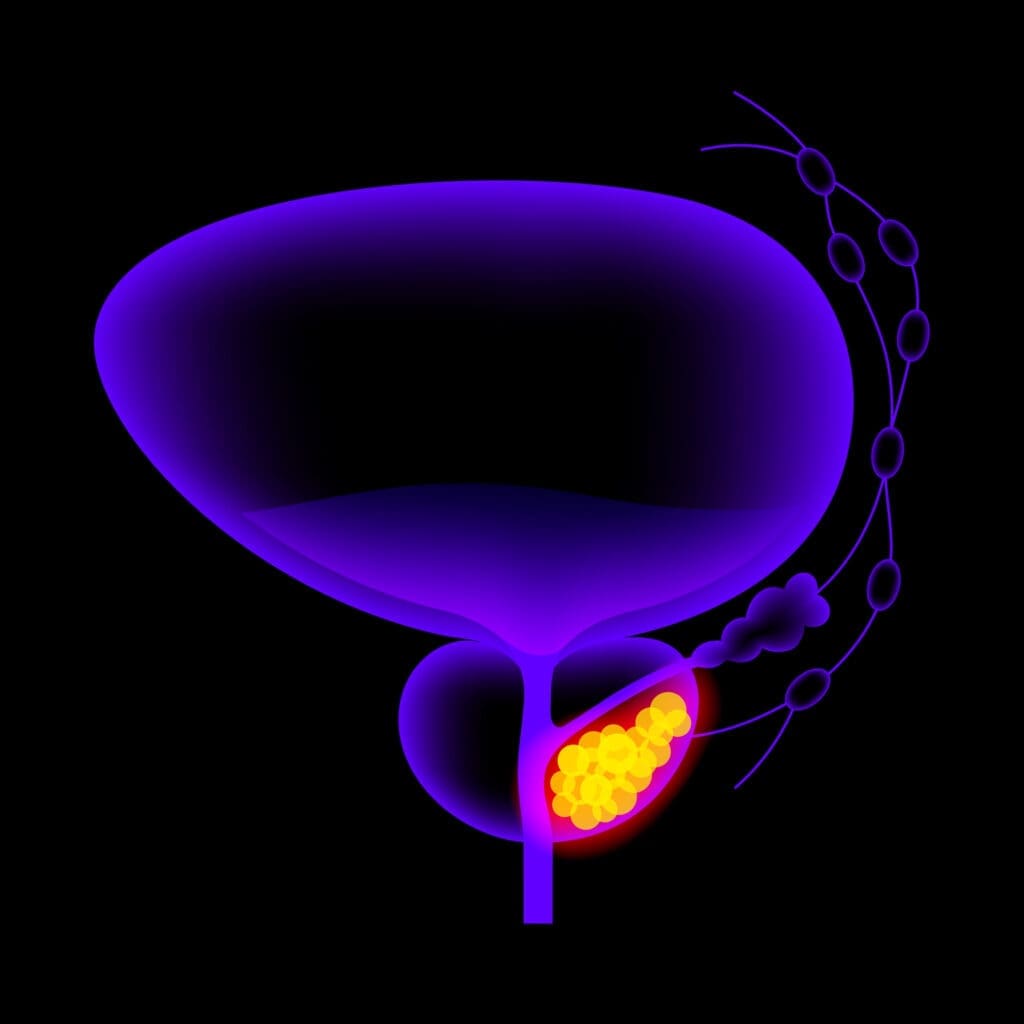

Located deep inside the groin between the base of the penis and the rectum, the golf-ball-sized prostate gland, along with the seminal vesicles behind the prostate, produces seminal fluid which mixes with sperm from the testes to help sperm travel. Prostate cancer occurs when healthy cells in the prostate begin to mutate and grow out of control. When the abnormal cells clump together, they form a cancerous tumor. Researchers still don’t have all the answers about what triggers changes to prostate cells, but know that genetics, family history, ethnicity, a high-fat diet and obesity are all risk factors.